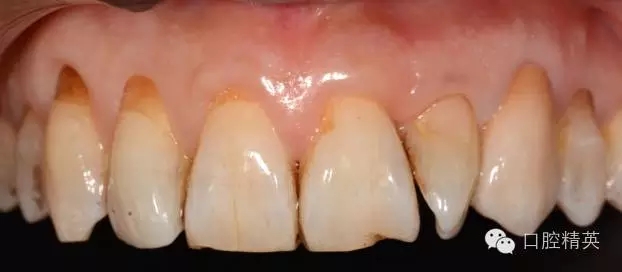

圖1 23口內(nèi)修復(fù)前情況:殘根位于齦上3MM,牙周無紅腫.

11.12.13頸部楔形缺損,探敏感,牙髓活力正常.

全口牙結(jié)石色素(+).